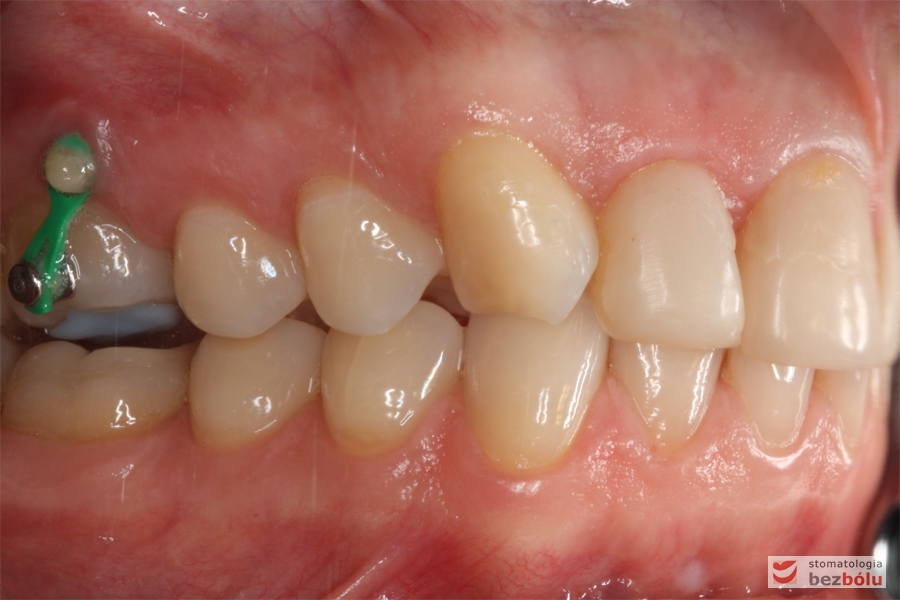

Zęby w dyskluzji - widok z boku, orotodontyczna intruzja zęba szóstego

Zęby w dyskluzji – widok z boku, orotodontyczna intruzja zęba szóstego